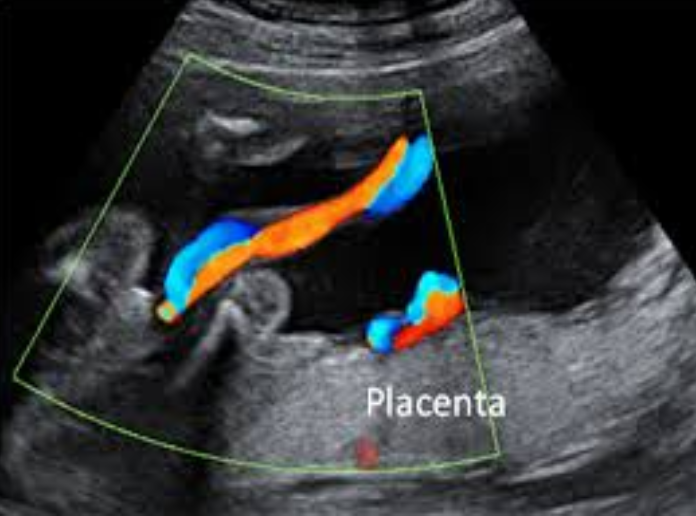

El ultrasonido del tercer trimestre que se usa en el perfil biofísico es una prueba que combina una ecografía y una prueba sin estrés para evaluar el bienestar del feto. Esta prueba mide cinco aspectos clave: movimientos fetales, tono muscular, movimientos respiratorios, cantidad de líquido amniótico y la frecuencia cardíaca del bebé. Se utiliza, sobre todo en embarazos de alto riesgo o si hay inquietudes sobre la salud del bebé, para determinar si el feto está sano.

Prueba sin estrés: Se colocan sensores en el abdomen para registrar la frecuencia cardíaca del feto en reposo y durante los movimientos. Evaluación ecográfica: Se utiliza un ecógrafo para examinar visualmente los cinco indicadores clave del bienestar fetal.

Movimientos corporales: Se observan si el bebé se mueve activamente. Tono muscular: Se valora la flexibilidad y contracción de las extremidades del feto. Movimientos respiratorios: Se comprueban si el feto realiza movimientos respiratorios. Líquido amniótico: Se mide el volumen de líquido que rodea al bebé. Ritmo cardíaco fetal: La frecuencia cardíaca del bebé es monitorizada.